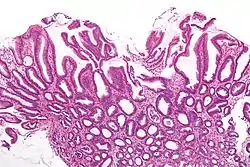

Micrograph of a reactive gastropathy. H&E stain.

Reactive gastropathy, is characterized histologically by:[2]

- Foveolar hyperplasia (black arrow), as a tortuosity in the "neck" region of the gastric glands.

- Scant or minimal inflammatory cells (white arrow), i.e. lack of large numbers of neutrophils and plasma cells..

- Smooth muscle hyperplasia in the lamina propria (in black oval).

The diagnosis is by examination of tissue, e.g. a stomach biopsy.